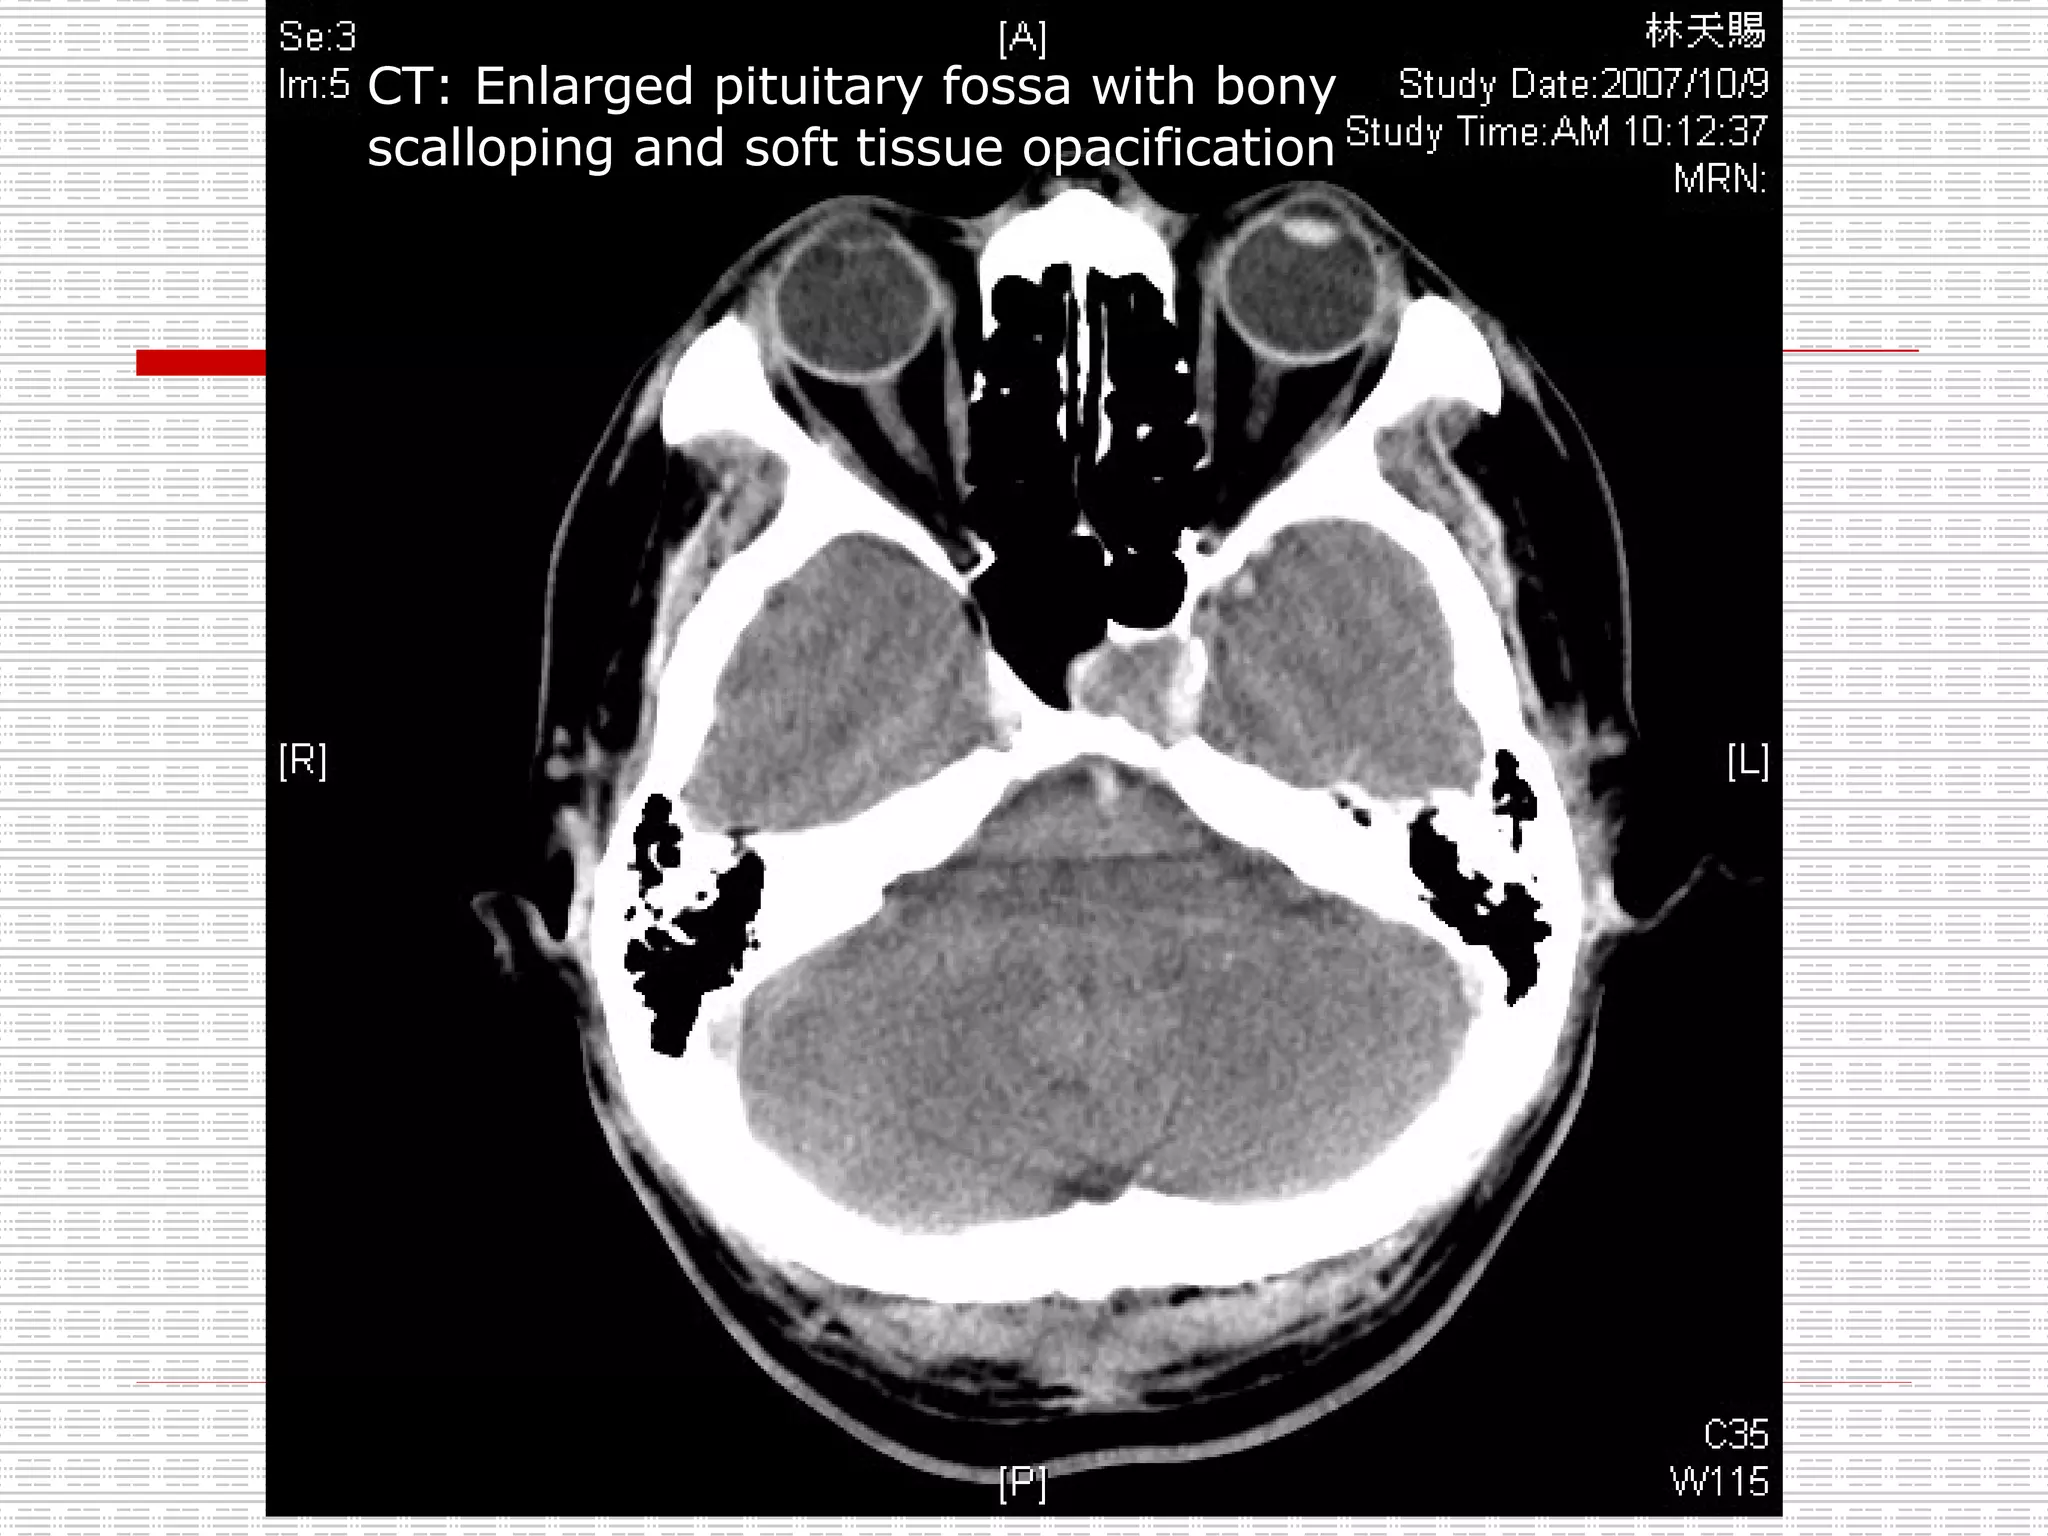

CT: Enlarged pituitary fossa with bony scalloping and soft tissue opacification

CT: Enlarged pituitaryfossa with bony scalloping and soft tissue opacification